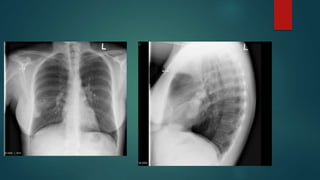

Pulmonary Stenosis

Mitral Stenosis